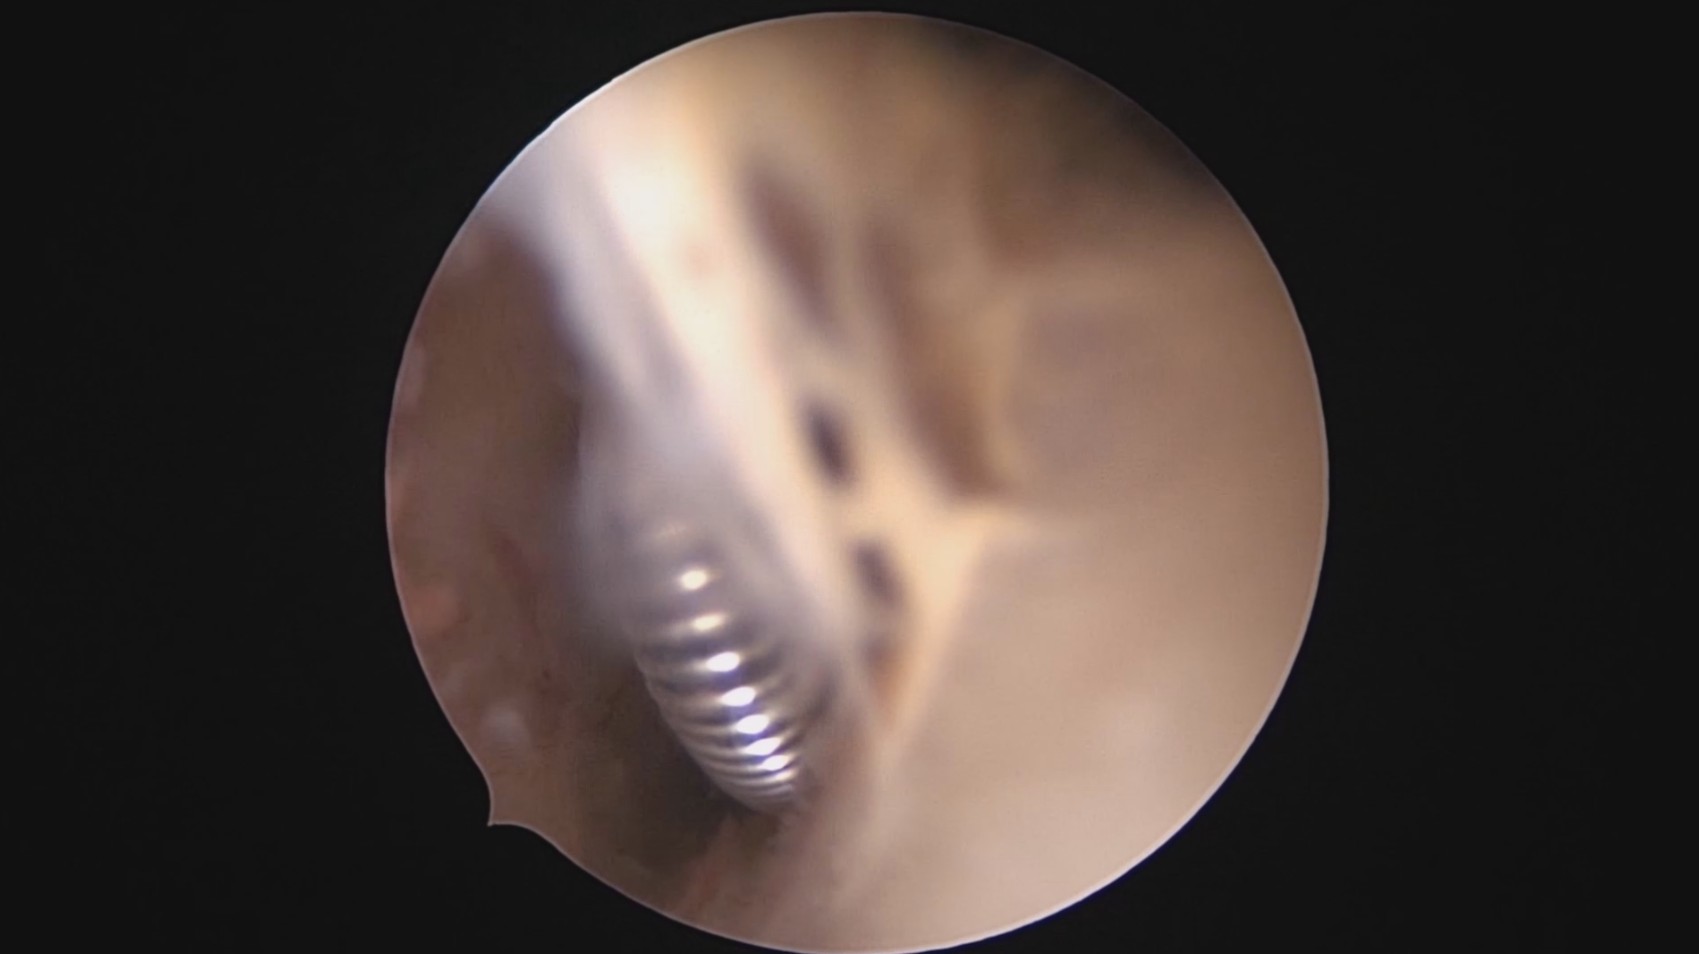

患者28岁,G7P3,顺产3次,完全纵膈子宫,单宫颈。2015年、2018年顺产,2019年左侧宫腔计划外妊娠行宫腔镜取胚及左侧宫腔放置γ环(推测既往妊娠左侧宫腔妊娠可能性大)。2023年4月带环受孕(应该为右侧宫腔妊娠),2023年12月足月阴道分娩,分娩时试图取出左侧宫腔内节育器,因操作困难,取环失败。2024年2月顺产后67天,要求取出宫内节育器,左手臂放置皮埋避孕棒。B超提示环距宫底1.1cm,环两翼分别距子宫前壁浆膜面0.4cm,距子宫后壁浆膜面0.3cm。宫腔镜术中膨宫困难,见宫颈管及宫腔少许淡黄色脓液流出,γ环逆时针旋转约80度,两臂指向左侧宫腔前后壁(2019年放置环时亦如此,因单侧宫腔前后径大于横径所致)。异物钳取出节育环,左右侧宫腔均见散在黄色机化组织,未取病检。